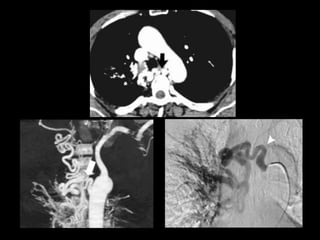

AngioTC Hemoptisis

• Diagnosticar causa del sangrado y obtener

mapa vascular angiográfico para embolización.

• Valorar patología pulmonar relacionada.

• Limitación: lesiones endobronquiales o

intracavitarias ocultas por sangrado.

Indicaciones:

• Hemoptisis masiva.

• Hemoptisis menor no controlable con tto médico.

• Pacientes candidatos a cirugía para reducir riesgo de

sangrado.

Riesgos:

• Embolización de arteria de Adamkiewicz

• Disección subintimal de aorta

• Resangrado tras embolización

Embolización